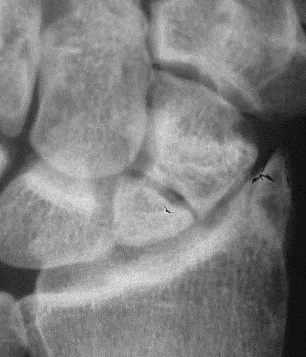

- Avascular necrosis (AVN):

narrowing+ sclerosis